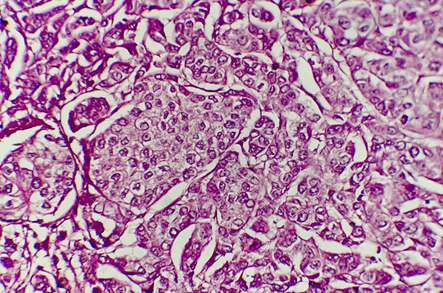

Treatment was enucleation of the right eye with patient consent because enucleation is the only therapy available in our environment (Figure 2).

Figure 2 Histological examination of the excisional specimen found a brownish lesion measuring 12mmX10mm+ Tumor proliferation of essentially spindle-shaped architecture with anisokaryotic and strongly nucleated nuclei in favor of a choroidal melanoma.

The tumor's epithelioid histological type and high mitotic power are factors with a poor prognosis.5 Chromosomal abnormalities: monosomy of chromosome 3 and 8, trisomy of chromosome 6 are indicators of poor prognosis.6 In this case, only one poor prognostic factor was found: tumor size, which was 12mmX10mm. The histological type was fusiform with strongly nucleated anisokaryotic nuclei.